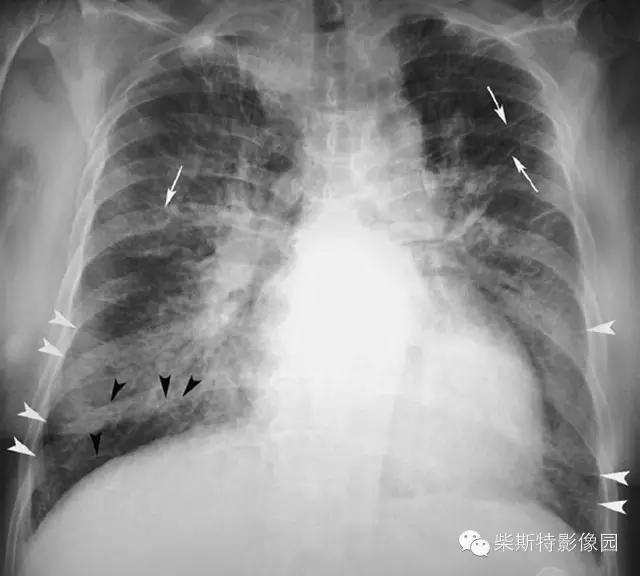

经典图像第一例:

小编标注:蓝色线是克氏A线,红色线是克氏B线,黄色网格状线是克氏C线。